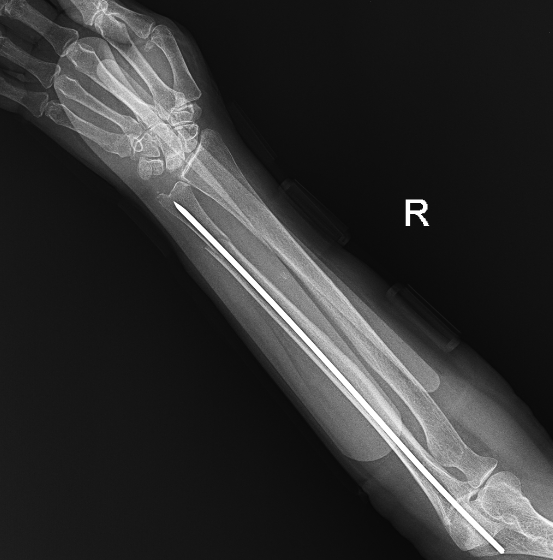

Hình ảnh xương đã được kết nối

Sau hội chẩn, ê-kíp lựa chọn phương pháp kết hợp xương xuyên đinh kín dưới hỗ trợ màn hình tăng sáng (C-arm). Đây là kỹ thuật ít xâm lấn, không cần mở ổ gãy, thực hiện qua đường rạch da nhỏ dưới hướng dẫn X-quang thời gian thực, giúp nắn chỉnh và cố định xương chính xác.

Phương pháp mang lại nhiều ưu điểm: giảm tổn thương phần mềm, hạn chế mất máu, rút ngắn thời gian phẫu thuật, giảm nguy cơ biến chứng và nhiễm trùng, giúp bệnh nhân giảm đau và phục hồi sớm. Đặc biệt phù hợp với người cao tuổi, nhiều bệnh lý phối hợp.